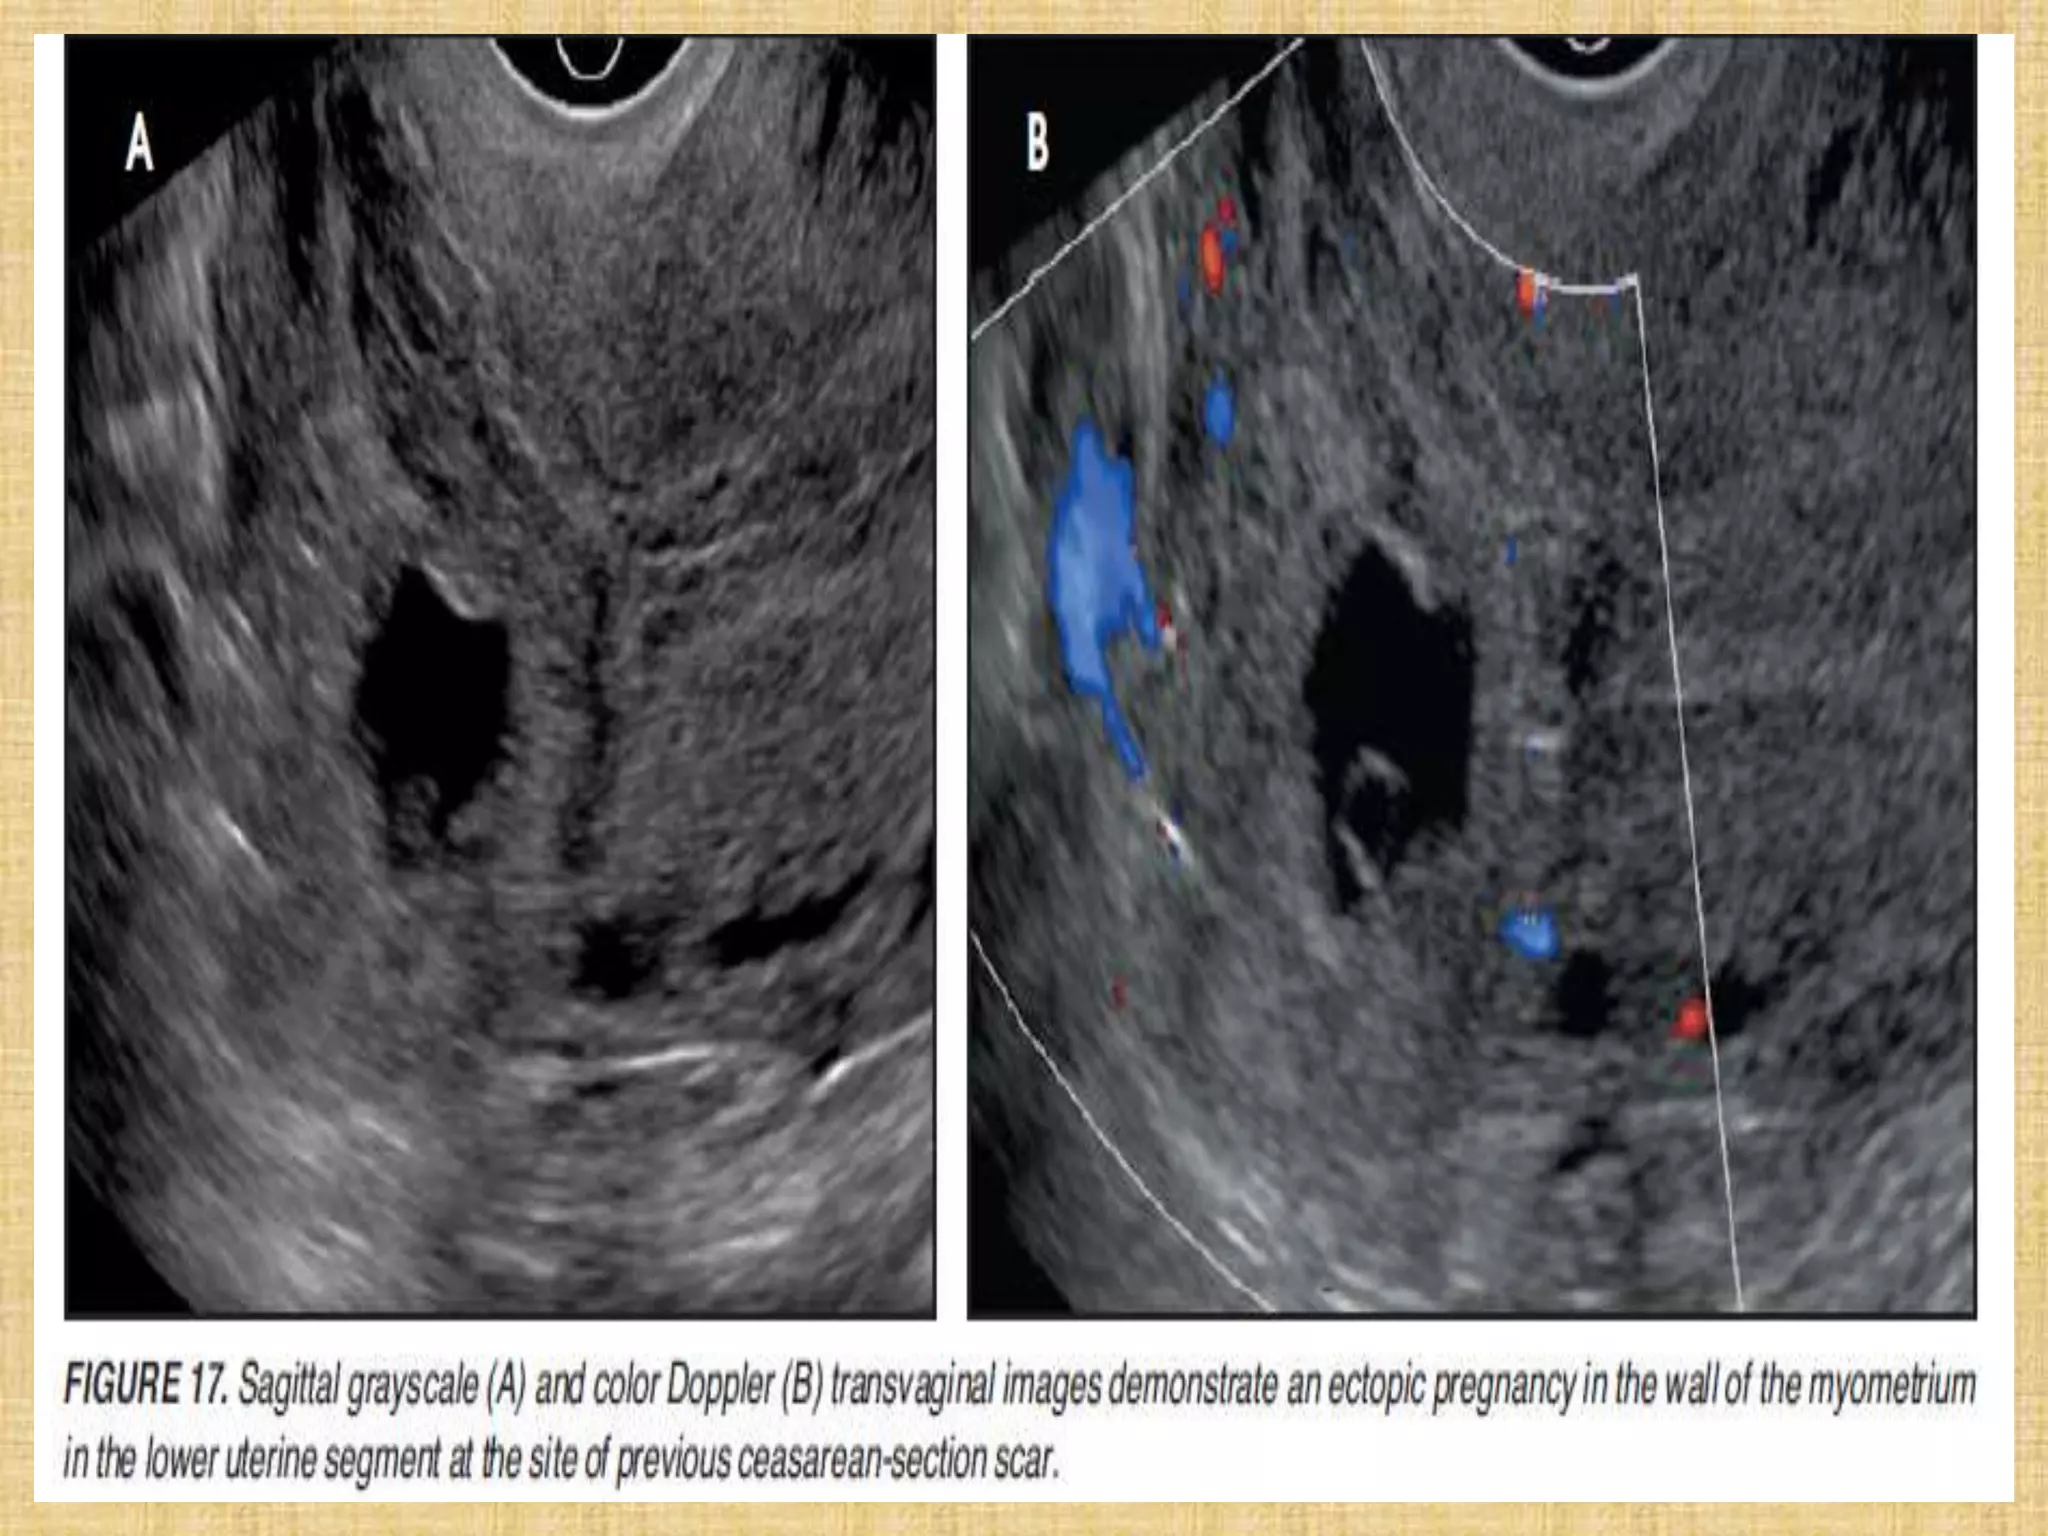

Live cervical ectopic pregnancy at 6 weeks gestational age. Sagittal view of

the cervix shows the gestational sac with an embryo (arrow) within the cervix.